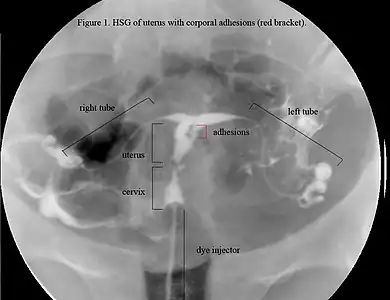

The history of a pregnancy event followed by a D&C leading to secondary amenorrhea or hypomenorrhea is typical. Hysteroscopy is the gold standard for diagnosis.[13] Imaging by sonohysterography or hysterosalpingography will reveal the extent of the scar formation. Ultrasound is not a reliable method of diagnosing Asherman's Syndrome. Hormone studies show normal levels consistent with reproductive function.

In an attempts to estimate the prevalence of AS in the general population, it was found in 1.5% of women undergoing hysterosalpingography HSG,[36] and between 5 and 39% of women with recurrent miscarriage.[37][38][39]